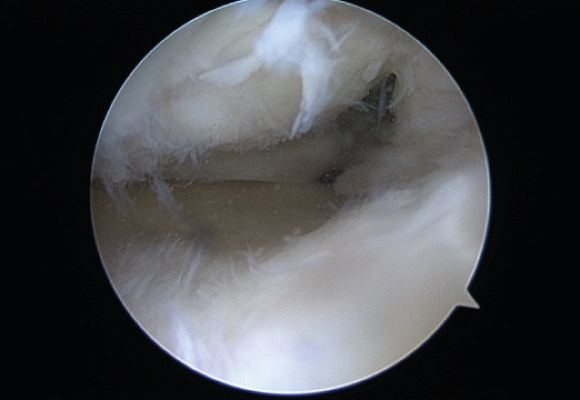

연골판봉합술

혈관이 있는 부위에 파열이 발생한 경우 연골판을 봉합해 주는 수술 시행

ㆍ환자 동의를 받은 자료이며, 이미지 사진은 실물과 다를 수 있습니다. (22.06.09)